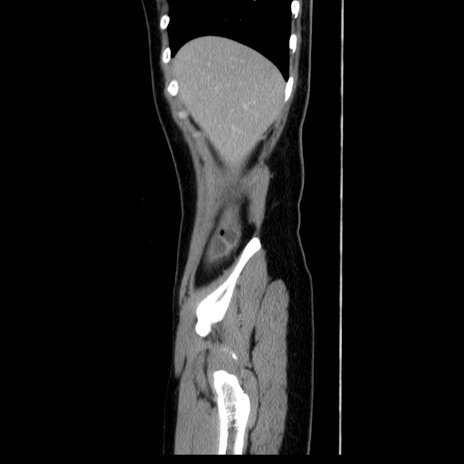

症例39(矢状断像)

【症例】40歳代女性

【主訴】上下腹部痛

【現病歴】2日目から下腹部痛あり。夜間は痛みで眠れなかった。昨日より上腹部痛と下痢が出現。臥位で痛みは軽快したため、休んでいた。本日になって臥位でも立位でも痛みが強くなってきたため救急要請。

【既往歴】子宮内膜症

【身体所見】部:平坦・軟、左上下腹部に圧痛あり、反跳痛あり。

【データ】WBC 21800、CRP 26.78

CT